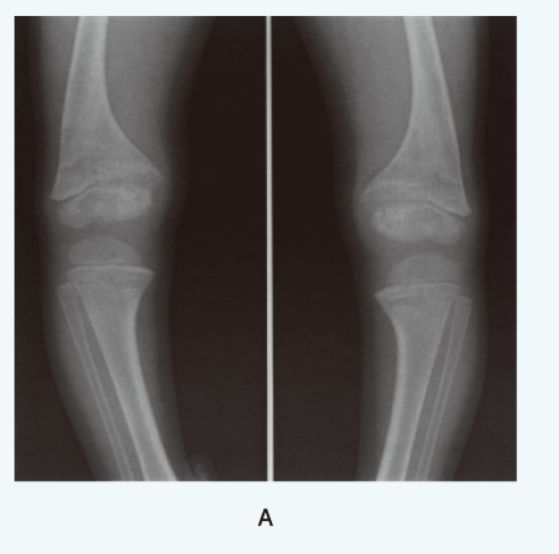

この図から、骨端部辺縁の拡大、杯状変形、辺縁不整などくる病に特徴的な初見が見える

また、膝の内反変形もみられる